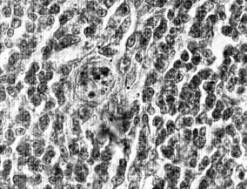

распадающимися ядрами (рис. 2). Контроль-2. Предварительное воздействие

лазера на икроножные

мышцы, подготавливаемые к операции, количество

мозгового вещества (14.26±1.67%), МИ

тимоцитов (8.9.6±1.03‰) и число клеток с пикнозом ядер (0.38±0.07%) не

отличались достоверно от соответствующих показателей у необлученных лазером

крыс до операции (контроль-1). Тимоциты

располагались сравнительно плотно. На

единицу площади мозгового вещества приходилось 1.06 тельца. Чаще встречались молодые

тельца, представленные скоплением 7-12 крупных клеток с гипертрофированными

ядрами, и тельца, в полости которых

появлялись 1-2 клетки с уплотненными ядрами или отмечались остатки клеточного

детрита (рис. 3). В опыте-2 через 30